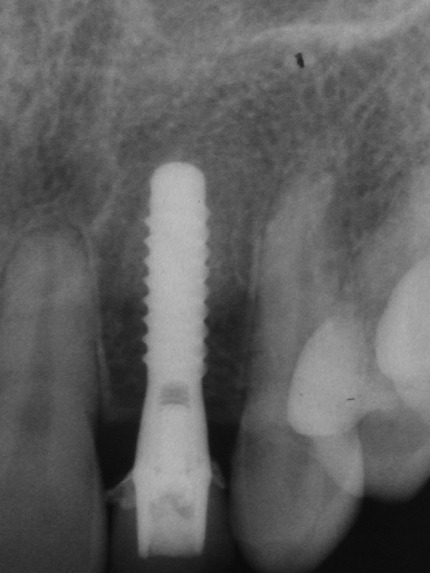

| Missing tooth | Implant placed |

| Temporary Crown | X-ray |